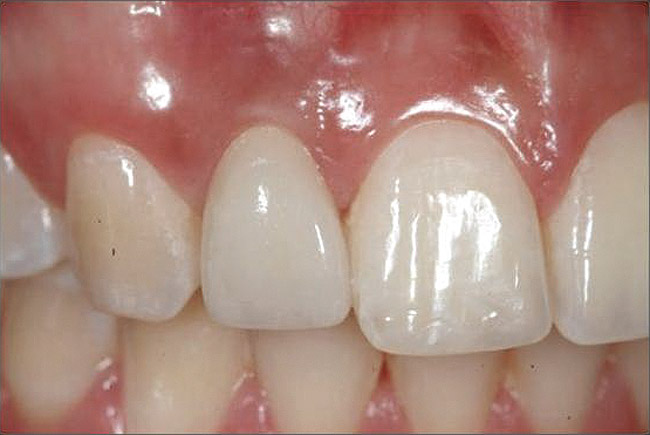

Figure 4  Characterization of the interproximal bone and tooth contacts: A periapical radiograph assists in measuring the distance from bone crest to the adjacent tooth contact points for missing tooth No. 8. The mesial bone crest to the adjacent tooth contact distance is < 5 mm, while the distal bone crest to adjacent tooth contact distance is > 6 mm (Fig 4). One-year following implant placement, conservation of these dimensions is revealed (Fig 5). The clinical photograph (Fig 6) of the lateral incisor adjacent to tooth No. 8 implant crown demonstrates that the absence of distal interproximal (papilla) fill related to the observed bone crest to contact distance exceeds 6 mm.

Figure 5  Characterization of the interproximal bone and tooth contacts: A periapical radiograph assists in measuring the distance from bone crest to the adjacent tooth contact points for missing tooth No. 8. The mesial bone crest to the adjacent tooth contact distance is < 5 mm, while the distal bone crest to adjacent tooth contact distance is > 6 mm (Fig 4). One-year following implant placement, conservation of these dimensions is revealed (Fig 5). The clinical photograph (Fig 6) of the lateral incisor adjacent to tooth No. 8 implant crown demonstrates that the absence of distal interproximal (papilla) fill related to the observed bone crest to contact distance exceeds 6 mm.

Figure 6  Characterization of the interproximal bone and tooth contacts: A periapical radiograph assists in measuring the distance from bone crest to the adjacent tooth contact points for missing tooth No. 8. The mesial bone crest to the adjacent tooth contact distance is < 5 mm, while the distal bone crest to adjacent tooth contact distance is > 6 mm (Fig 4). One-year following implant placement, conservation of these dimensions is revealed (Fig 5). The clinical photograph (Fig 6) of the lateral incisor adjacent to tooth No. 8 implant crown demonstrates that the absence of distal interproximal (papilla) fill related to the observed bone crest to contact distance exceeds 6 mm.